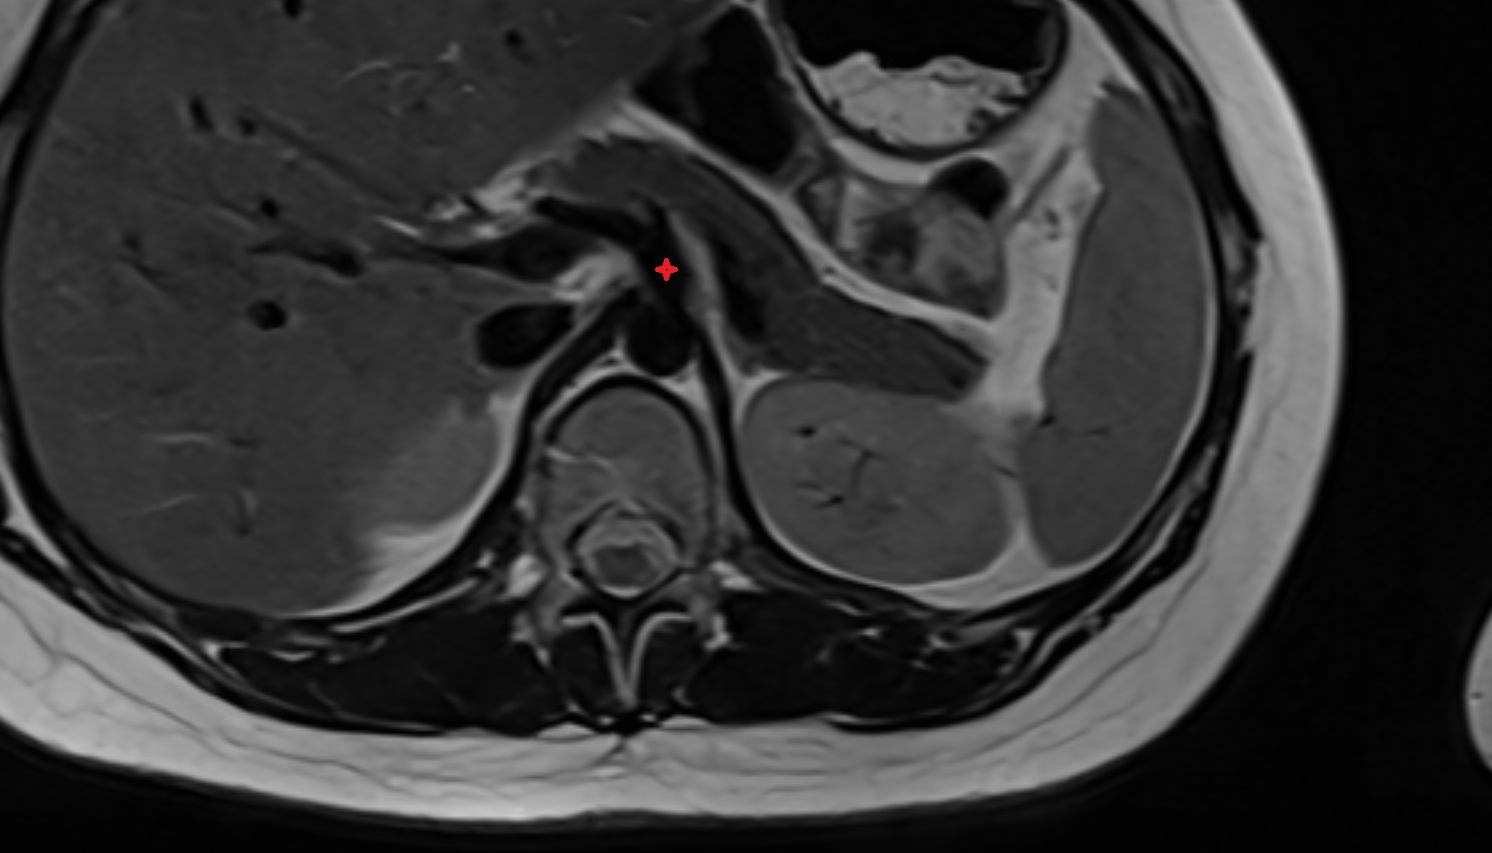

- kidneys

- Right kidney

- Left kidney

- Kidney cortex (Renal cortex)

- Renal medulla

- Renal pyramids